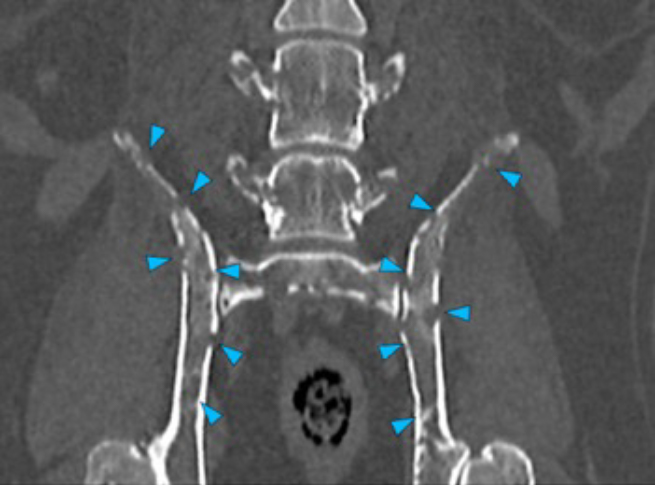

There are multiple osteolytic lesions affecting almost all the vertebral bodies (red arrows). Some of them are areas of permeative or moth-eaten lysis, while others converge into geographic lesions. They affect all the different portions of the vertebra (vertebral body, spinous and transverse processes, etc.) and involve the medullary cavity of the bone (blue arrows), and some of them cause lysis of the cortex (green arrows). Lumbar vertebral bodies more severely affected.

The osteolytic lesions have soft tissue attenuation that shows moderate and slightly heterogeneous post-contrast enhancement. In some of the vertebrae, the lesions cause lysis of the cortex and extend into the vertebral canal (orange arrows) causing variable degree of compression of the spinal cord and cauda equina (blue arrows). At the level of the vertebral bodies of T7, T8, T9 and T12 the lesions extend into the ventral and central aspect of the vertebral canal causing a mild compression of the spinal cord. At the level of T13, L1, L4 and L5 the lesions extend into the ventral and central aspect of the vertebral canal, causing moderate compression of the spinal cord. At the vertebral body of L6 the lesion extends into the ventral and central aspect of the vertebral canal, at the mid-aspect of L6, occupying approx. 90% of the diameter of the vertebral canal causing a severe compression of the cauda equina. At the level of L7, the lesion extends into the ventral and both lateral aspects of the vertebral canal, causing severe compression of the cauda equina.